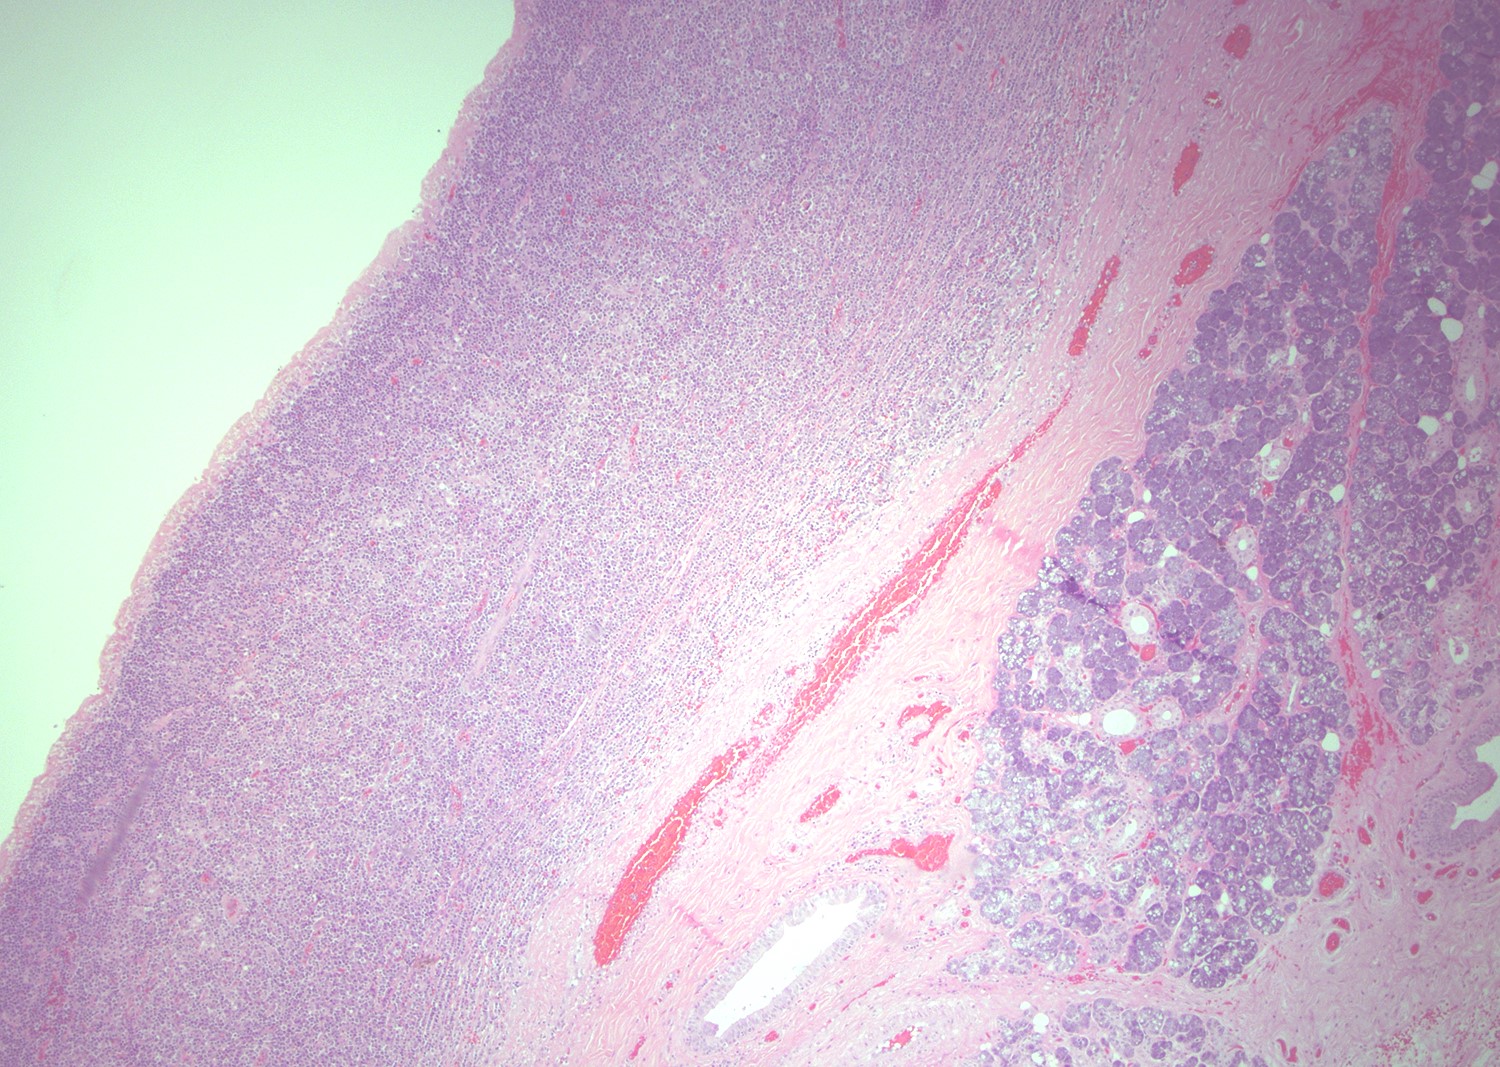

- Most cases show a unilocular cyst with a thin stratified squamous lining

- Epithelium is surrounded by dense polymorphous lymphoid tissue with germinal centers and sinusoidal spaces

- Lymphocytes frequently permeate the epithelial cyst lining cells

Microscopic (histologic) images